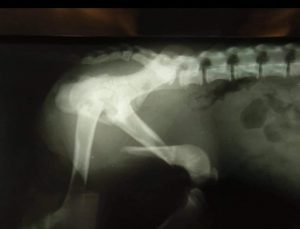

PER TRASPARENZA PUBBLICHIAMO LE RADIOGRAFIE POST INTERVENTO DELLA PRINCIPESSA DJURDJA 🌸

LE FRATTURE SONO MULTIPLE, LE PIÙ IMPORTANTI SONO LA FRATTURA DEL GOMITO DELLA ZAMPA ANTERIORE SINISTRA E LA FRATTURA DELLA COSCIA DELLA GAMBA POSTERIORE SINISTRA E DEL BACINO.